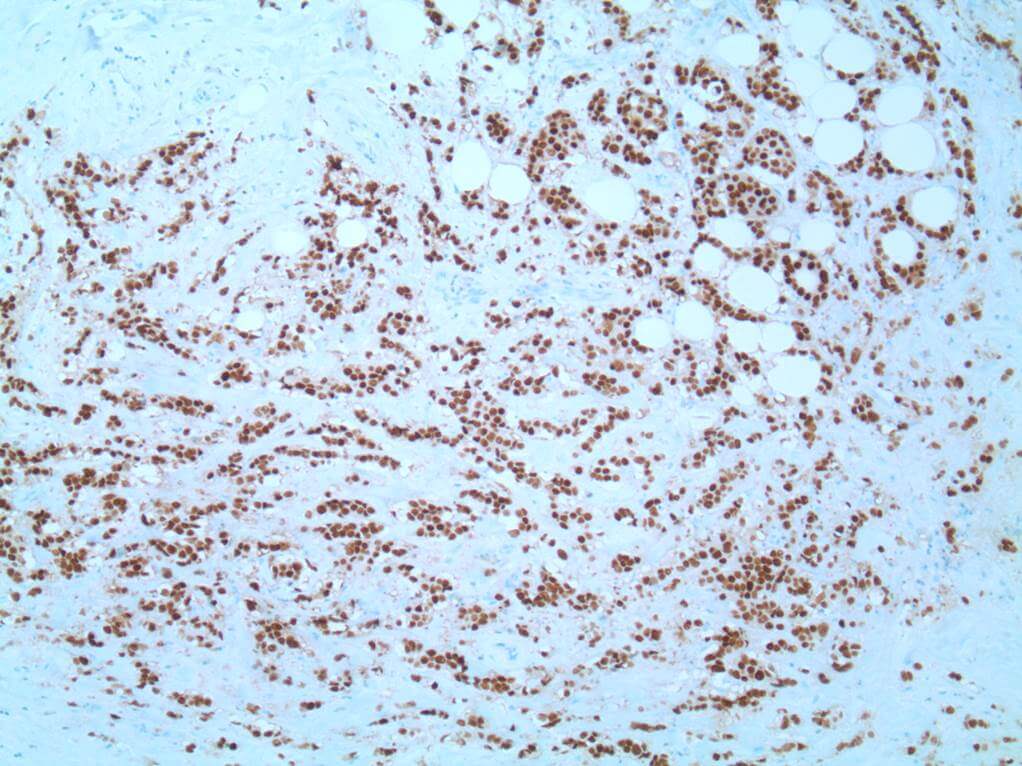

The hormone receptors for estrogen (ER) and progesterone (PR) are detected by immunohistochemistry in formalin fixed, paraffin embedded sections of invasive breast cancer and is a positive result in as little as 1% of tumour nuclei showing expression (Figure 4 – ER positive case). Proper handling of the specimen including optimal fixation is essential for reliable results. Around 80% of invasive carcinomas are ER positive with higher grade tumours less likely to be positive.

This image depicts grade 3 invasive carcinoma. Professional medical imaging for clinical reference and educational purposes. [umbracoNodeId=9801]

Figure 4: Grade 3 invasive carcinoma